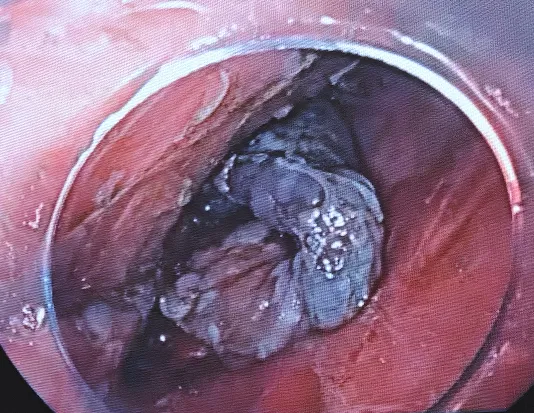

11:06边补水边剥离11:08病灶切下来了。

11:09创面处理,对创面可疑的出血处给予电凝止血

手术结束一般术后一周复查胃镜如果术后病理浸润到了粘膜下层,建议外科手术,不同意外科手术的患者也要建议放化疗